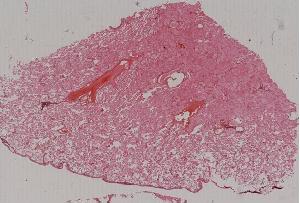

12.急性肺淤血